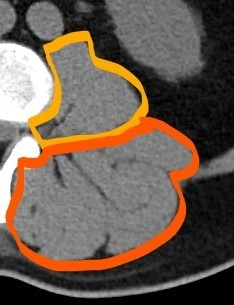

붉은색: 등심, 오렌지색: 안심

CT상에서 보이는 회색 근육이고, 검은색지방이다. 좌측 사진을 보면 근육 사이사이 검은색 선이 보이는데 지방이다. 물론 사람에서는 그렇고, 소고기에서 이 지방마블링이라 한다.

CT상에서 보면, 이 안심은 복벽 안에 있는 요근(psoas muscle)이다. 이 근육이 수축 시, 허리가 ㄱ 자로 굽어진다. 등심(ecector spinae muscle, 척추 기립근)이 수축하면 허리가 펴지고, 안심(psoas muscle, 요근)이 수축하며 허리가 굽어진다. 등심이 동전의 앞면이라면, 안심은 동전의 뒷면이다.

등심은 복벽 밖에 있고, 길고 두꺼우며, 기름이 많다. 반대로 안심은 복벽 안에 있고, 얇고 가늘며, 기름이 적다. 운동으로 등심(ecector spinae muscle, 척추 기립근)은 부피를 키울 수 있지만, 안심(psoas muscle, 요근)은 키우기 어려워 육질이 훨씬 부드럽니다.